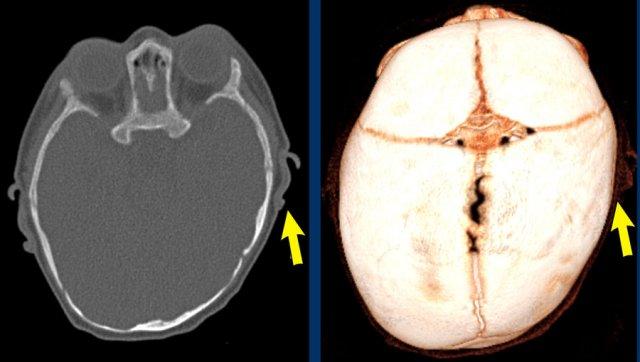

CT 3D

Hình ảnh cho thấy các đường khớp còn mở ở một trẻ có đường khớp trán đã đóng về mặt sinh lý (mũi tên).